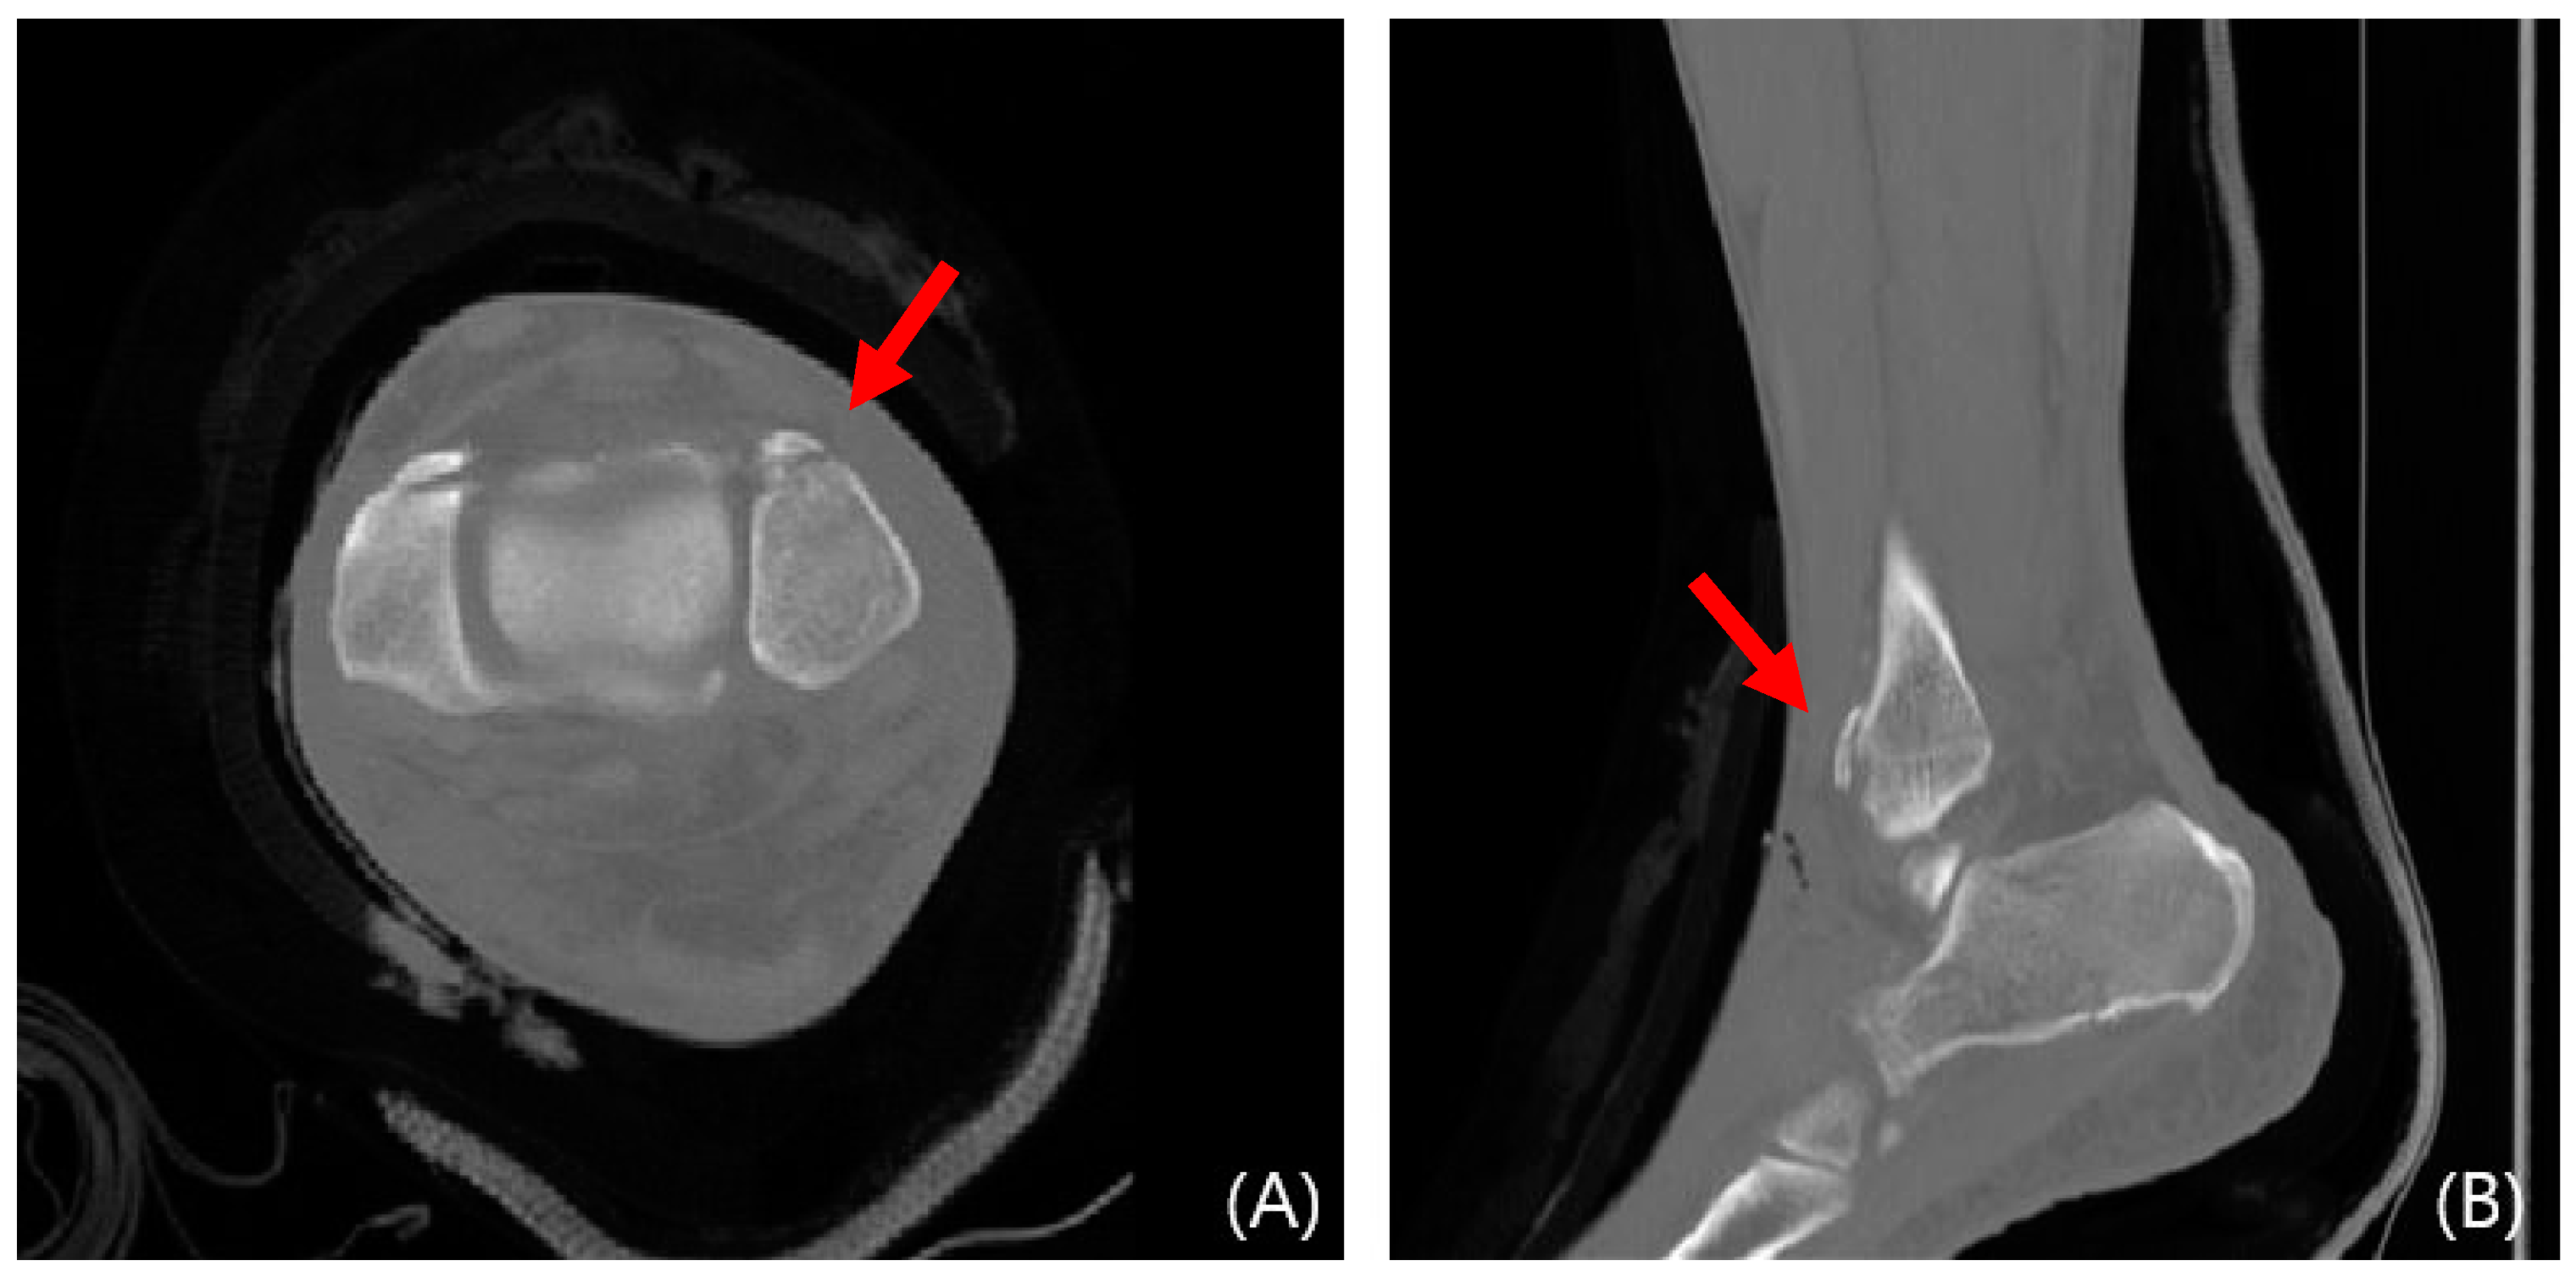

2.3. Radiological Evaluations

This study evaluated syndesmosis reduction by analyzing postoperative axial CT images captured 1 cm proximal to the tibial plafond (Table 1 and Figure 1) [16,17,18,19]. Four radiographic measurements were chosen and assessed with a PACS image viewer software (Dejaview2 version 1.0, Dongwun Information Technology, Republic of Korea). Two independent observers, blinded to patients’ clinical outcomes and current complaints, objectively evaluated the measurements. The process was repeated after a 6-week interval to ensure reliability.

Figure 1. Radiologic measurements. (Red line) (a) Direct anterior difference and direct posterior difference. (b) Fibular translation. (c) Fibular rotation (Red line).